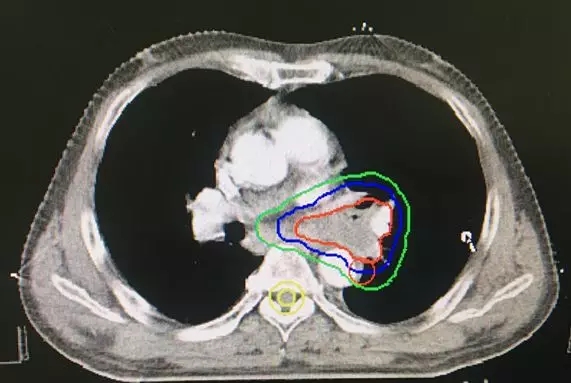

基于以上观点,科室现广泛开展了分子影像(PET-CT)引导下的三维调强放射治疗。该技术是利用PET-CT图像与定位CT图像进行同步融合,在融合图像上勾画调强放疗靶区(即生物靶区),使放疗靶区勾画达到了分子水平,有效识别了肿瘤与非肿瘤区域,明确了肿瘤精确体积及边界,提高了放射治疗“打靶”的准确性、精确性、有效性,更加有效的保护了肿瘤周围正常组织,降低了周围正常组织放疗相关并发症,进一步提高了肿瘤放疗的局部控制率。科室将PET/CT融合定位技术与CT模拟定位图像融合技术应用于中心型肺癌伴肺不张患者,取得了满意的治疗效果。

图2:PET/CT融合后进行精准放疗靶区勾画